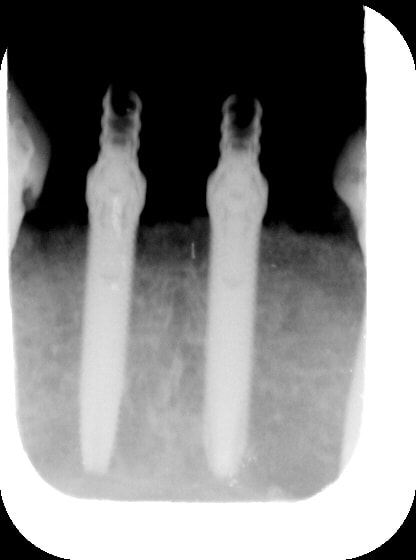

rx du haut...8 mois après...

Gin8m1 wfymdg - Eugenol

Gin8m2 rdbaga - Eugenol

Gin8m3 zsapdx - Eugenol

l' implant en 25 aurait pu etre un peu plus distalé....mais plus court...